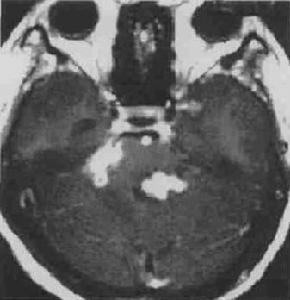

2.MRI掃描結核球在T1加權像上為低或略低信號,在T2加權像上大多信號不均勻,表現為低等或略高信號。結核球中心乾酪樣壞死在T2加權像上呈高信號,也可呈模糊不清的同心圓狀分層像,周圍包膜呈低信號,並有高信號的水腫帶環繞。這種有水腫帶包繞者,表明結核球尚未成熟。MRI比CT掃描更能顯示病變的範圍。腦幹的結核球與神經膠質瘤兩者在MRI都表現長T1和短T2,同樣病灶周圍水腫在T2加權像上均高信號,因此,兩者在MRI圖像上不易鑑別。